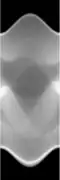

Concretely, for the two-dimensional Radon transform, the dual transform is given by: In the context of image processing, the dual transform is commonly called back-projection[4] as it takes a function defined on each line in the plane and 'smears' or projects it back over the line to produce an image.

Compared with the Filtered Back-projection method, iterative reconstruction costs large computation time, limiting its practical use. However, due to the ill-posedness of Radon Inversion, the Filtered Back-projection method may be infeasible in the presence of discontinuity or noise. Iterative reconstruction methods (e.g. iterative Sparse Asymptotic Minimum Variance[10]) could provide metal artefact reduction, noise and dose reduction for the reconstructed result that attract much research interest around the world.

Explicit and computationally efficient inversion formulas for the Radon transform and its dual are available. The Radon transform in dimensions can be inverted by the formula:[11] where , and the power of the Laplacian is defined as a pseudo-differential operator if necessary by the Fourier transform: For computational purposes, the power of the Laplacian is commuted with the dual transform to give:[12] where is the Hilbert transform with respect to the s variable. In two dimensions, the operator appears in image processing as a ramp filter.[13] One can prove directly from the Fourier slice theorem and change of variables for integration that for a compactly supported continuous function of two variables: Thus in an image processing context the original image can be recovered from the 'sinogram' data by applying a ramp filter (in the variable) and then back-projecting. As the filtering step can be performed efficiently (for example using digital signal processing techniques) and the back projection step is simply an accumulation of values in the pixels of the image, this results in a highly efficient, and hence widely used, algorithm.